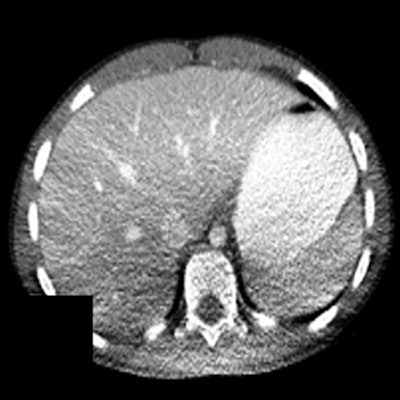

This can cause nonuniform noise in the image following reconstruction. Moreover, possible shading artifacts may occur due to beam hardening from changes in the mean beam energy that can lead to artifactual changes in organ density (Fig. 4).7

Szczykutowicz et al investigated the effect of patient positioning on CT number that is used to diagnose clinical conditions. They found that a mispositioning of 4 cm and 6 cm above the isocenter resulted in statistically significant differences in the Hounsfield unit (HU) standard deviation. A 4-cm magnification led to standard deviations of -15 ± 5 and -8 ± 2 HU for midthorax posterior and abdomen posterior, respectively. A 6-cm magnification led to standard deviations in the range of 13-20 HU for high thorax and mid thorax posterior.7